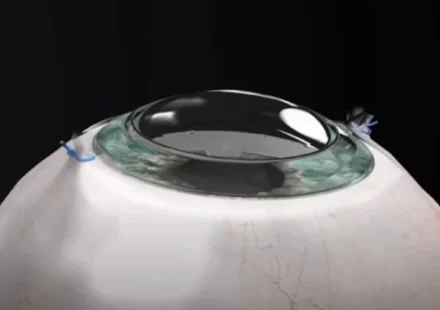

Израильская компания CorNeat Vision разработала искусственную роговицу, позволяющую 78-летнему мужчине, который был слепым в течение десяти лет, полностью восстановить зрение. Преимущество этого имплантата, получившего название KPro, заключается в том,…